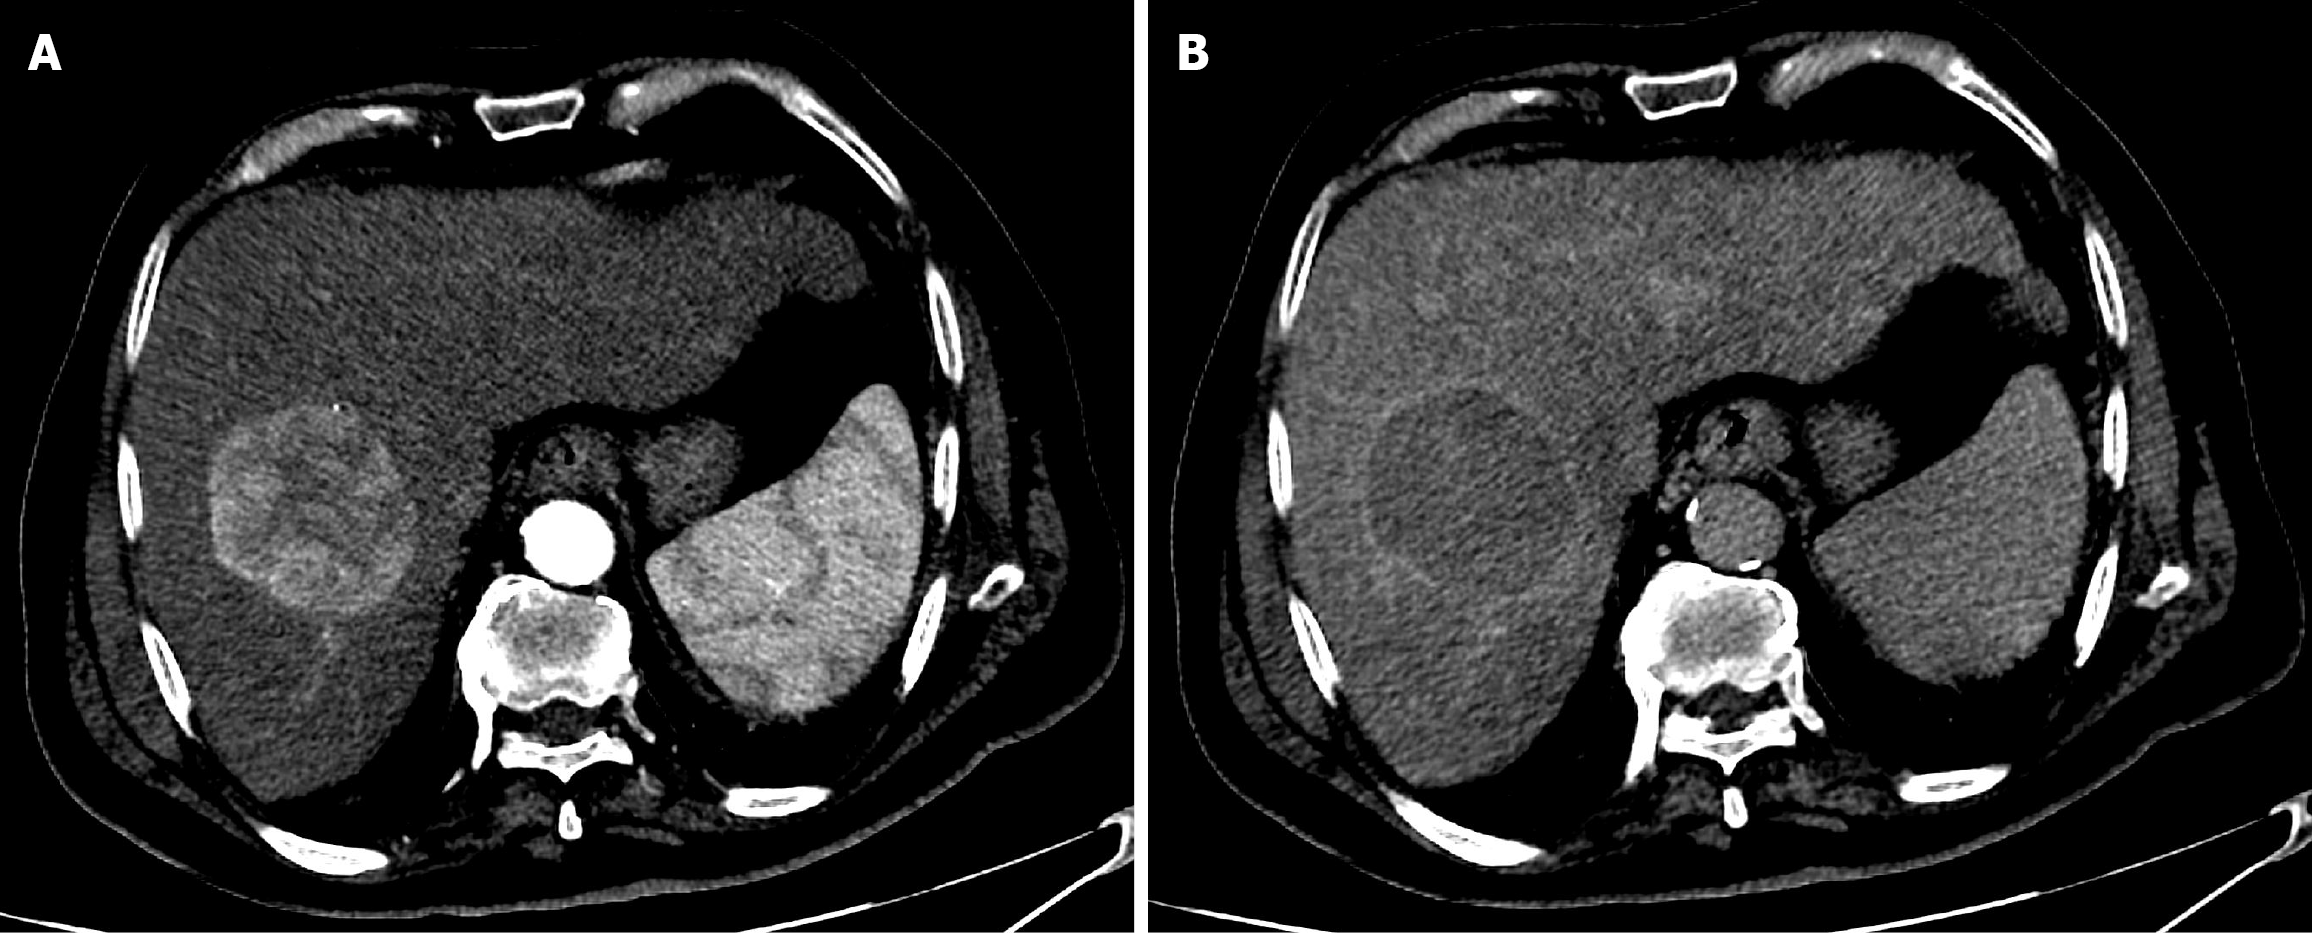

Figure 12 Six-year follow-up computed tomography of the abdomen after the second drug-eluting bead transarterial chemoembolization in Case 2.

A: Pre-contrast computed tomography (CT) demonstrated dense, progressive peripheral concentric calcification surrounding the treated hepatic mass; B: Arterial phase CT showed a non-enhancing mass, consistent with sustained complete response.